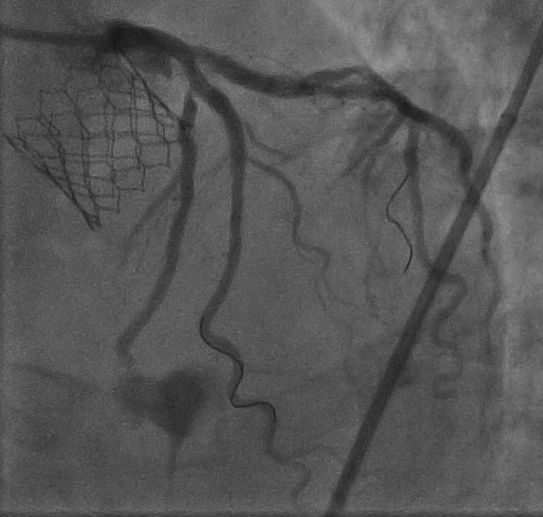

- Coronary angiogram revealed 99% ostial LCx disease, 95% ostial D1 with moderate LM disease.

Angiogram showed severe ISR with 99% ostial LCx and 95% ostial D1 disease.

Final angiogram